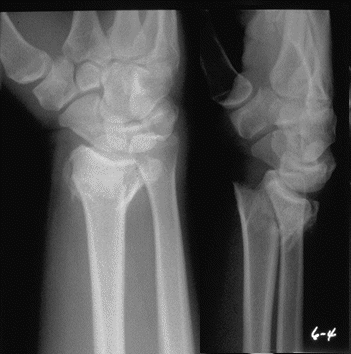

Case 2 Preop